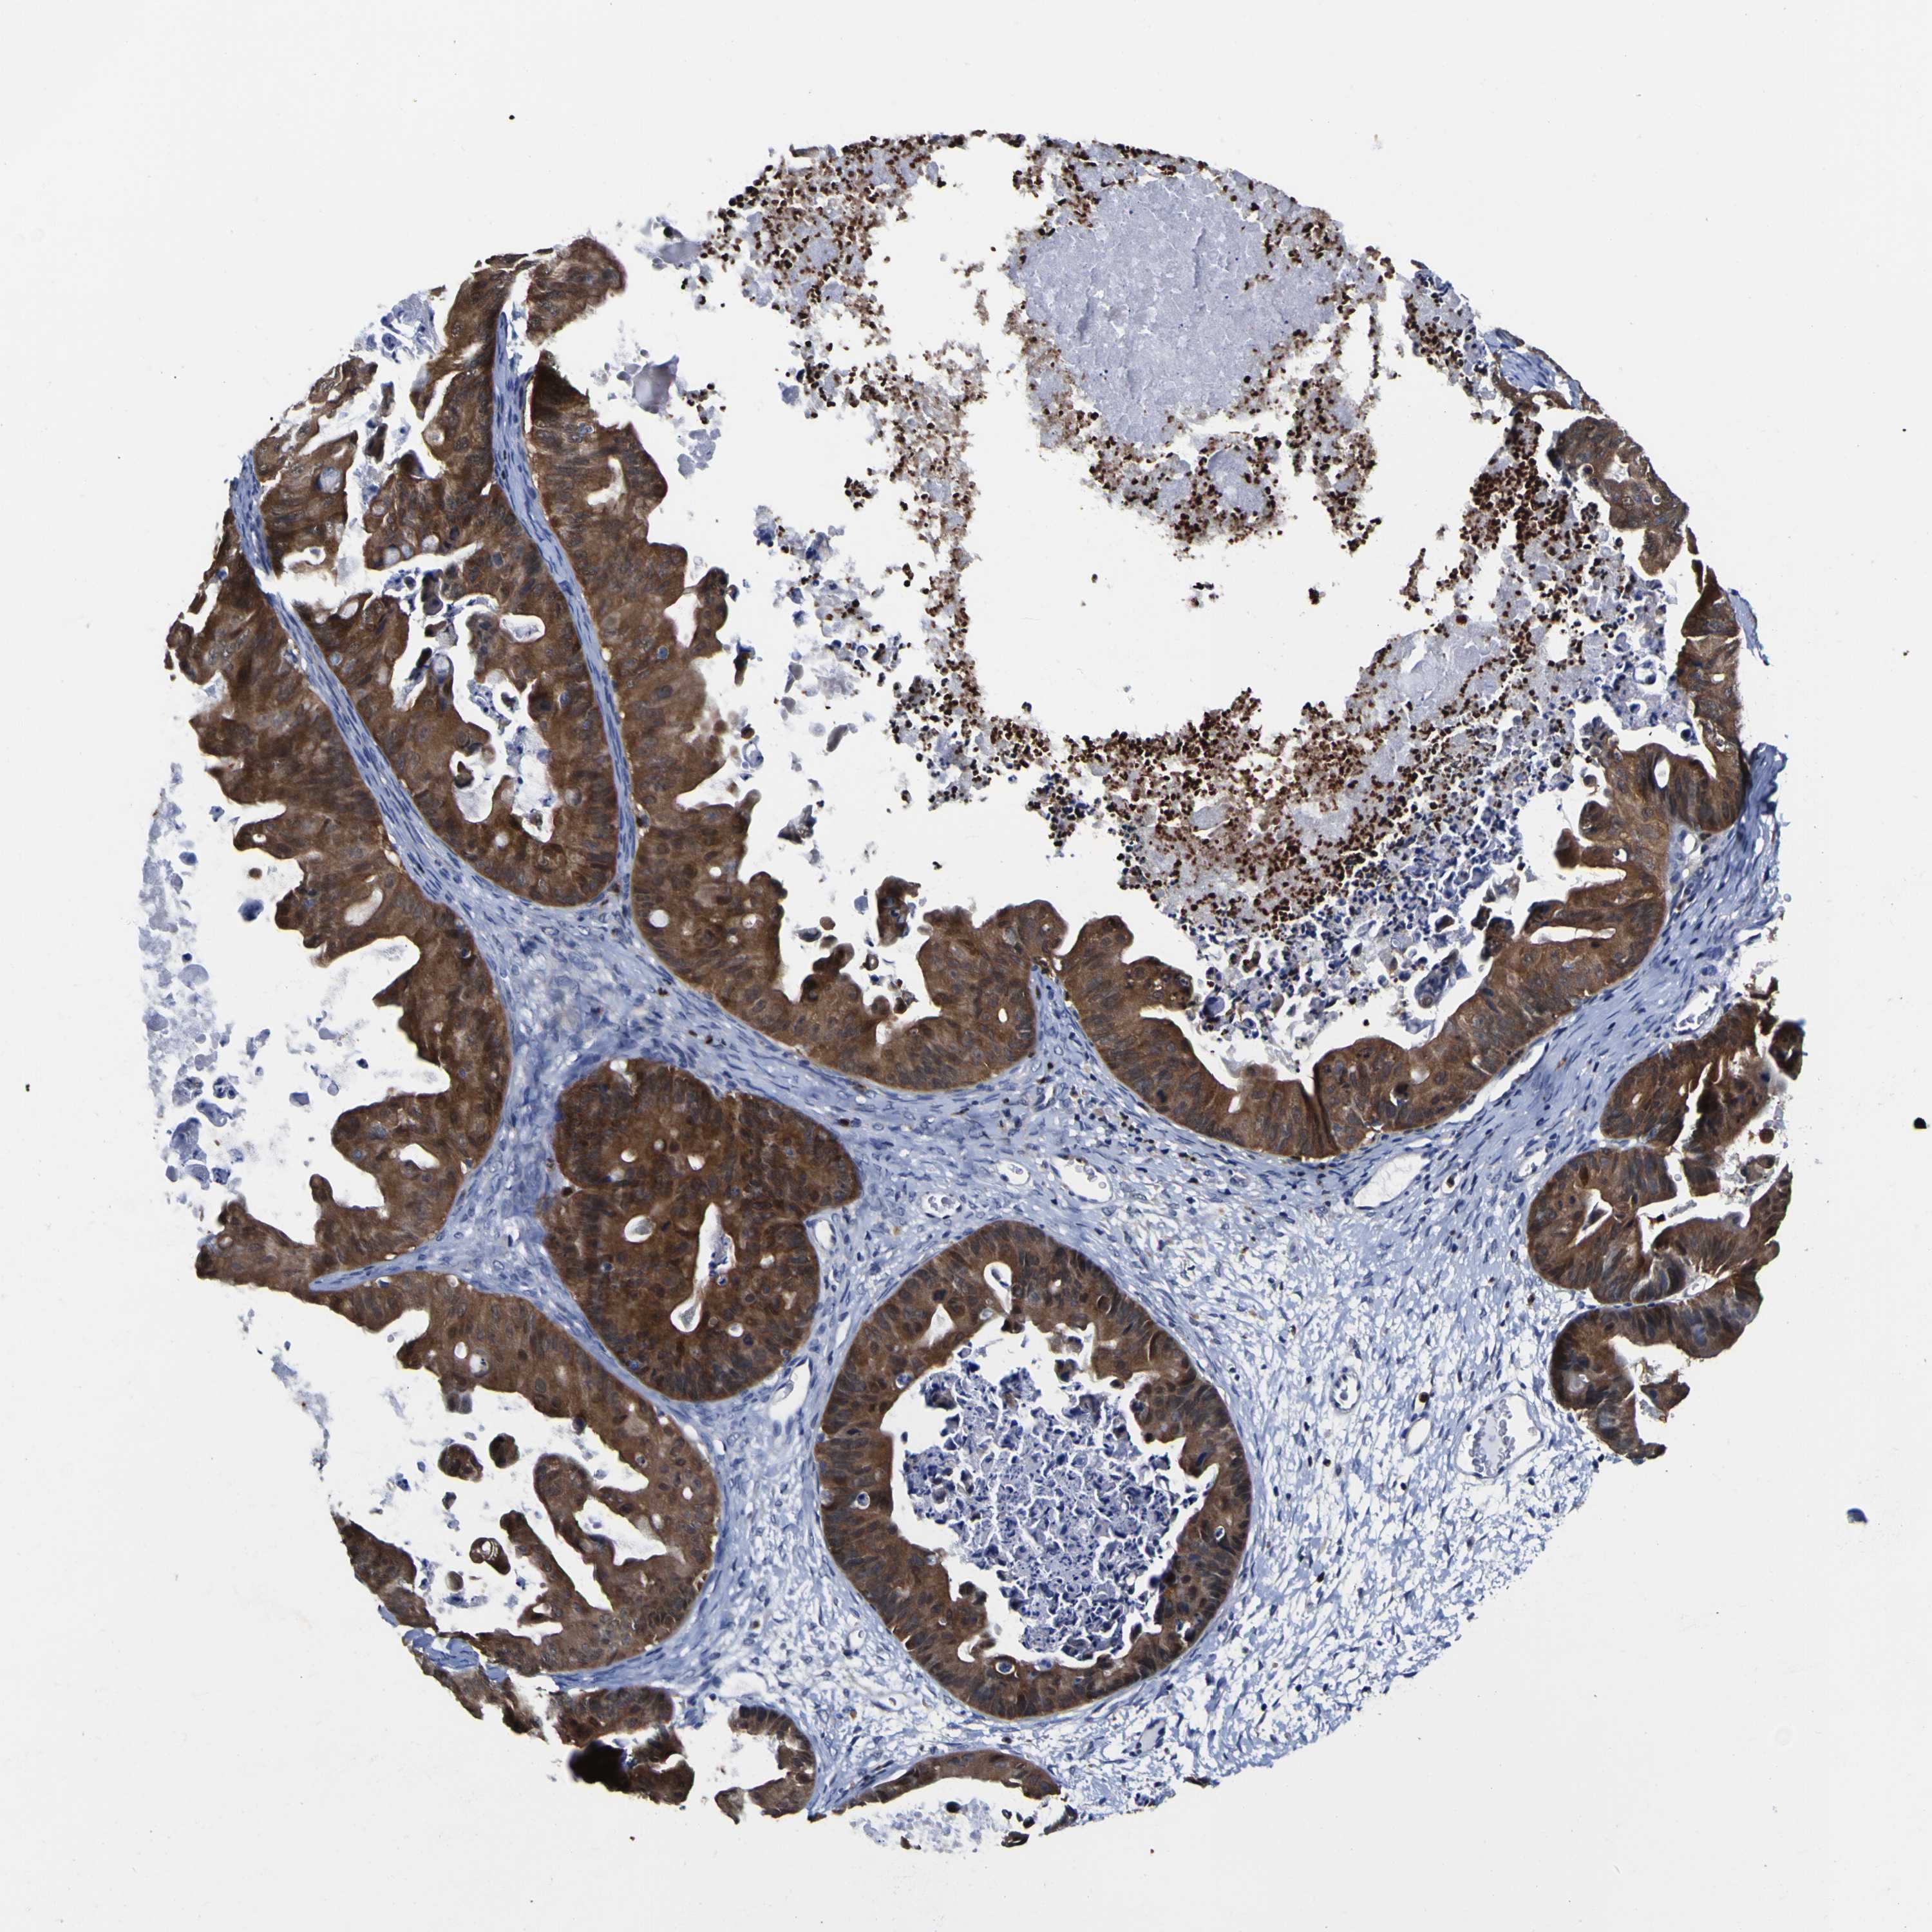

OVARIAN CANCER - Protein expressioni

A mouse-over function shows sample information and annotation data. Click on an image to view it in a full screen mode. Samples can be filtered based on level of antibody staining by selecting one or several of the following categories: high, medium, low and not detected. The assay and annotation is described here.

Note that samples used for immunohistochemistry by the Human Protein Atlas do not correspond to samples in the TCGA dataset.

Antibody stainingi

Antibody staining in the annotated cell types in the current human tissue is reported as not detected, low, medium, or high, based on conventional immunohistochemistry profiling in selected tissues. This score is based on the combination of the staining intensity and fraction of stained cells.

Each image is clickable and will lead to virtual microscopy that enables deeper exploration of all samples and also displays staining intensity scores, fraction scores and subcellular localization as well as patient and tissue information for each sample.

Antibody CAB003775

Carcinoma, NOS